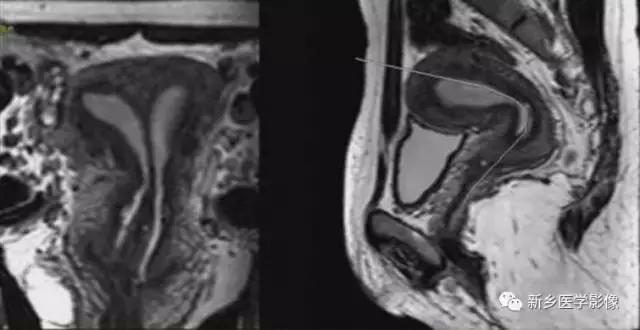

上图:双子宫:双侧子宫及宫颈完全分离

双子宫:双侧子宫完全分离,右侧阴道积血(阴道斜隔),宫腔积血,呈长T2信号。

右侧先天性肾缺如。